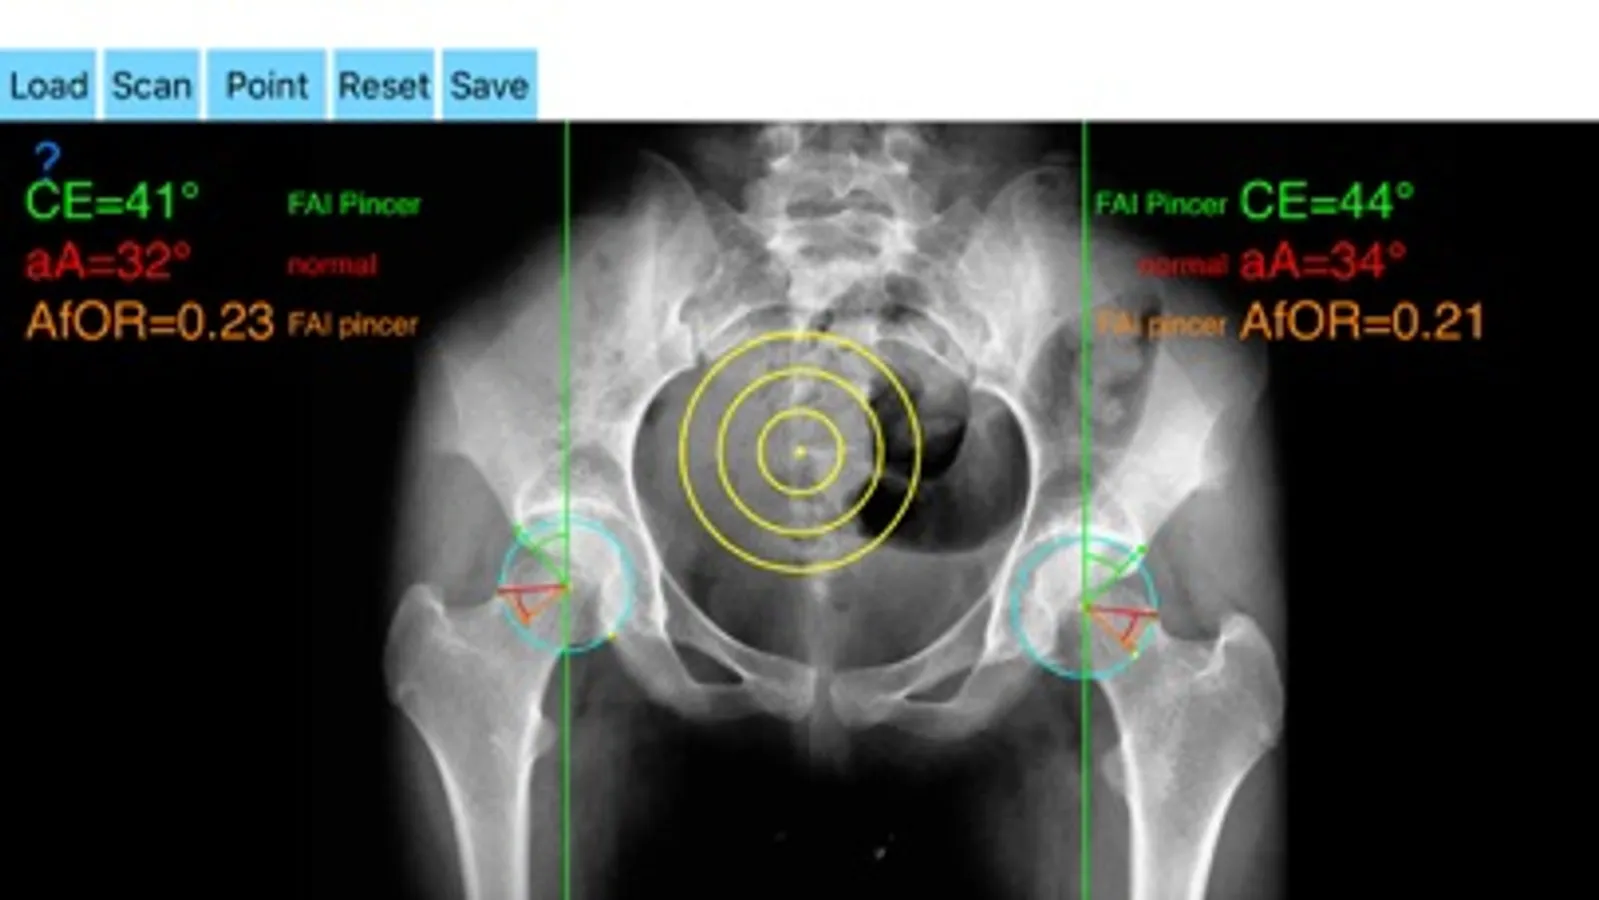

Offers a very convenient way to determine the most accurate possibly lines in order to measure the angles. By the aid of a circular transparent template, the points of interest are marked accurately. The circular template help to detect and mark easily, the alpha point - where the radius of the curvature of the femoral head first exits the circle of best fit corresponding to a circular head - real turning point of asphericity of femoral head

The drawn lines between points, allows app to estimate in radiographs, Center-Edge Angle (CE), α - angle (aA) and the anterior femoral offset ratio (AfOR). The measured values are compared with values from normal reference database. In case the measured angles are beyond the normal range, the hip is categorized as normal, dysplastic, borderline dysplastic hip and the type of femoroacetabular impingement (FAI) deformity namely cam type, pincer type or mixed is printed over the screen accordingly. Measures by the app are not affected by the X-ray projection.